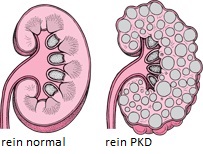

La PKD est une maladie d’origine génétique qui touche le persan mais aussi l’exotic shorthair et le british shorthair. Elle est caractérisée par le développement progressif et irréversible de kystes dans les reins aboutissant à une insuffisance rénale chez l’animal adulte voire âgé. La PKD fut découverte en 1967.

Les chats atteints développent des kystes au sein des reins qui se multiplient et grossissent. Ces kystes détruisent progressivement les reins et l’animal développe une insuffisance rénale chronique. Les symptômes sont un amaigrissement chronique, une baisse de l’état général, une polyuro polydipsie (le chat boit plus et urine plus) et des vomissements.

Lorsque l’insuffisance rénale se développe chez un jeune chat, le pronostic est généralement très sombre. En revanche, si la maladie se déclare chez un chat adulte voire âgé, cela n’influence par forcément son espérance de vie car l’évolution peut être très lente.